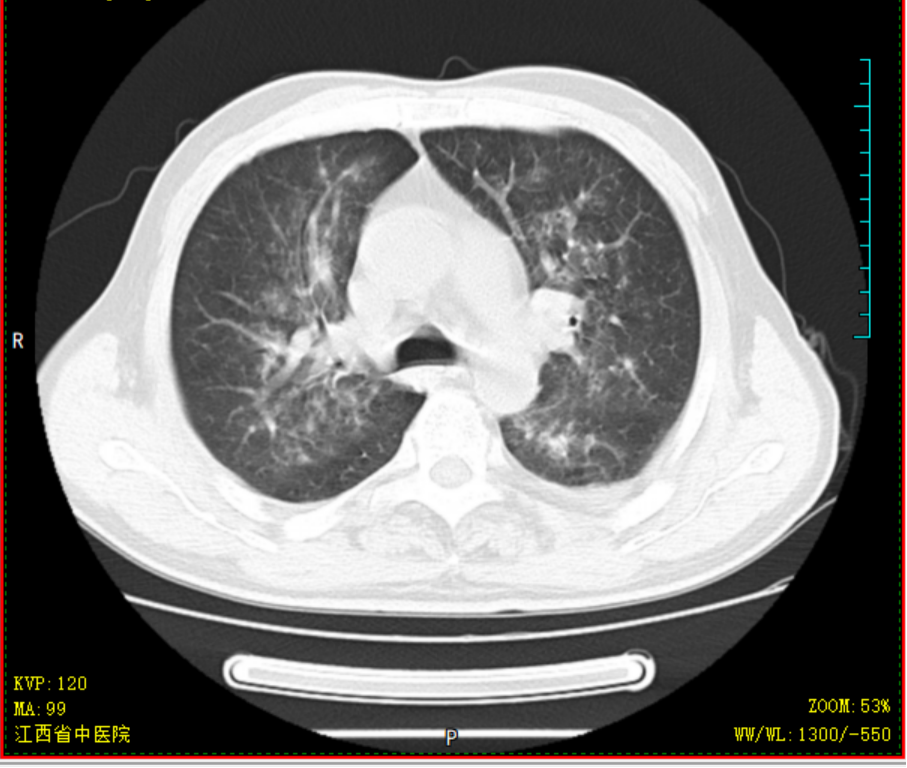

胡大爷,男,69岁,2020-4-14因“头晕乏力”就诊某省级医院,完善骨髓细胞学等检查后诊断为AML-M2a型,中危组;排出化疗禁忌症后,予标准DA方案化疗治疗,化疗过程中出现持续高热,热峰39.5℃,肺部感染、重症肺炎,恶心呕吐明显,予美罗培南+万古霉素抗感染,伏立康唑抗真菌感染,输注红细胞、血小板等治疗,化疗结束后复查骨髓细胞学示AML-NR骨髓象(急性髓系白血病未缓解骨髓象),经40天住院治疗病情平稳后出院,出院时体重减轻10kg。因为恐惧化学治疗,自行停化疗。2020-07-23患者因疲劳乏力加重就诊于我院,要求中医调理,入院查血常规示重度贫血、血小板减少,生化示肝功能不全、高尿酸;骨髓提示AML-NR骨髓象(急性髓系白血病未缓解骨髓象)。入院后予中药汤剂益气养血,并热敏灸温通经络。经治疗后患者乏力疲劳、贫血明显改善,排除治疗禁忌后,08-13起减低剂量化学治疗,同时口服我科经验方参芪杀白汤益气养血、扶正祛邪抗肿瘤,同时调理脏腑气机减少化疗不良反应,起增效减毒之功;热敏灸疗法灸肺腧穴固护肺卫之气预防外邪入侵,灸脾腧穴、肾腧穴固先后天之本促进气血化生。全程未出现呕心呕吐、骨髓抑制等常见不良反应,09-07骨髓细胞学示AML-CR骨髓象(急性髓系白血病完全缓解骨髓象)、白血病微小残留MRD提示阴性。2020-09-08返院行中西医结合方案抗白血病治疗,过程顺利,结束治疗后09-15出院 。经西医结合治疗不但是患者的症状改善明显,同时提高患者生活质量,同时保证了患者的临床疗效。